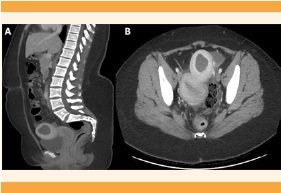

En la ecografía abdominopélvica se sospechó una malformación congénita uterina, pues se visualizó el útero izquierdo ligeramente tubular, de tamaño normal, con un pólipo endometrial en su interior, y adyacente a la imagen se observó una masa compatible con hemiútero derecho, de 52 x 49 mm, con contenido líquido hematológico retenido (hematometra) de 25 mm. El hemiútero no tenía conexión aparente con el cuello uterino ni con la porción contralateral del útero (Figura 1). El ovario izquierdo se visualizó de tamaño y características normales, con microfolículos y eje mayor de 3.2 cm, rodeando por fuera y por delante al ovario derecho, también de tamaño y aspecto normales; se observó una estructura quística alargada y en forma de codo, con contenido ecogénico de 65 x 15 mm, sugerente de hematosalpinx (Figura 2). La tomografía abdominopélvica confirmó la coexistencia del hemiútero derecho, de 55 x 54 mm, hipervascular, degenerado, con colección hemorrágica interna de 30 mm (Figura 3), e hidrosalpinx derecho. La ecografía y la tomografía no demostraron malformaciones renales. Figura 4

Figura 3 Tomografía abdominal, A) corte sagital y B) transversal. Hemiútero derecho en plano más anterior, de 55 x 54 mm hipervascular, degenerado, con colección hemorrágica interna de 30 mm, compatible con hematometra.